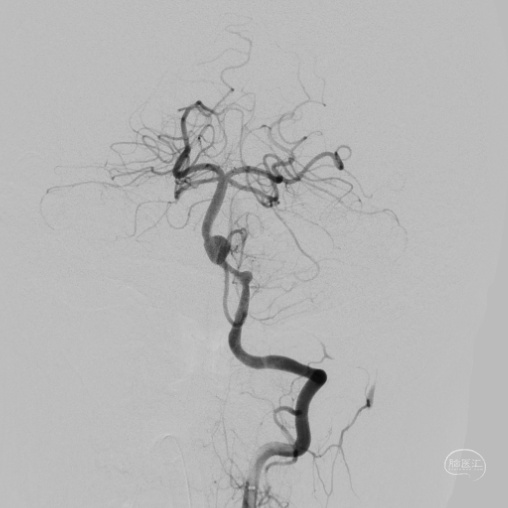

DSA:

3D重建显示基底动脉下部、双椎结合部、左椎多发夹层动脉瘤:

双抗5天后行左侧椎动脉多发夹层动脉瘤Pipeline™ Flex 血流导向密网支架植入术。

将Phenom™ 27微导管超选进入左侧大脑后动脉内,释放一枚3.25×35mm Pipeline™ Flex血流导向密网支架,远端定位在动脉瘤以远7mm,在动脉瘤处推密,近端定位在PICA起始部上端或远端,支架打开顺利。导引导管内推注替罗非班12mL,支架导管及微导管常规按摩,促进支架贴壁。

术后造影显示动脉瘤内造影剂滞留明显,载瘤动脉通畅。